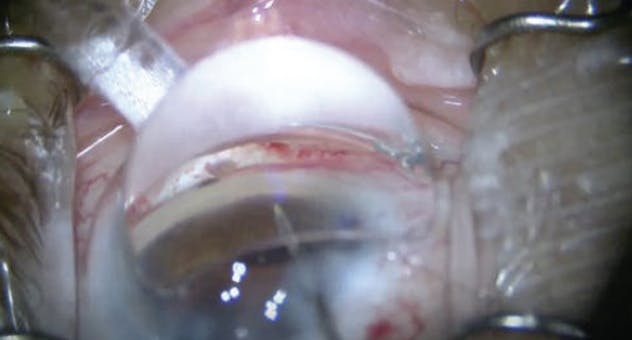

Laser Cataract Surgery Combined With iTrack Canaloplasty and Hydrus Microstent

Billy Pan, MD